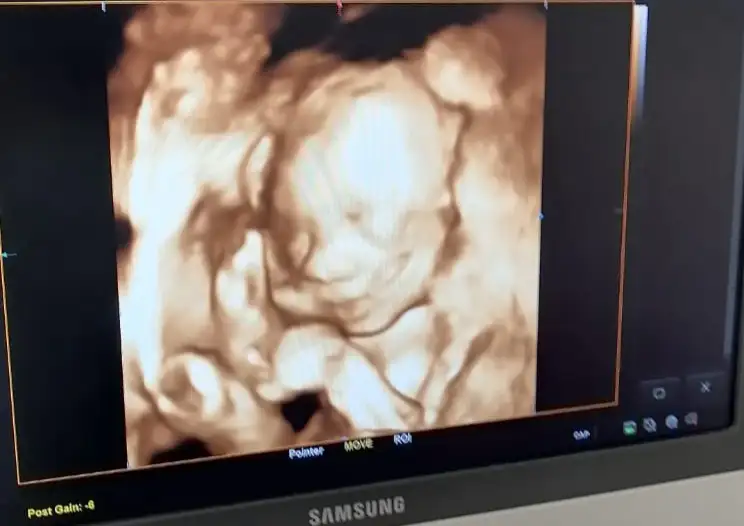

Kizlar bende simdi muayeneden çıktım 24+5 herseyin iyi oldugunu soyledi cok sukur ❤️😊 Boyu 31 santim sanirim hala haftasina gore kucuk ama bisey demedi ona, kilosuna gayet iyi dedi 749 grammis minnos 😊 Renkli ultrason simdi vermiyim sirtini da donmus zaten dedi iyi dedim :)

Babasi gibi kafasini arkaya atmis 😂